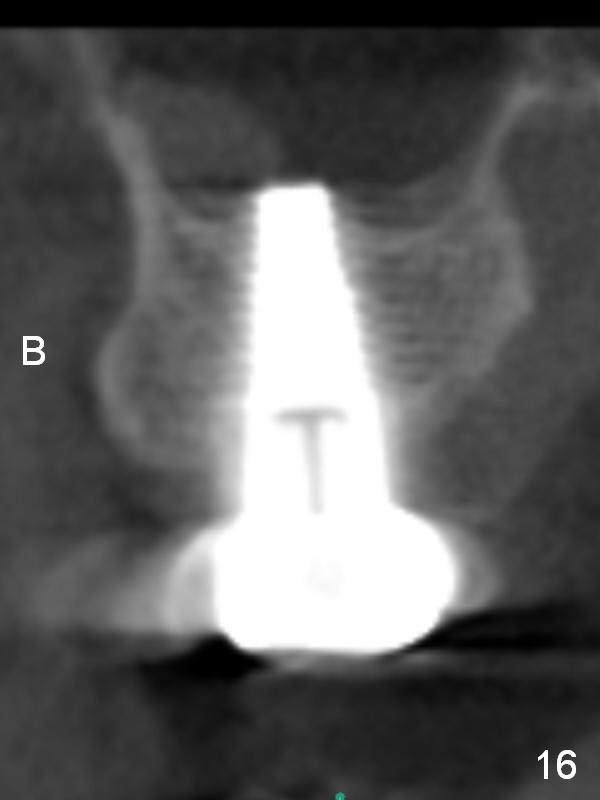

A 42-year-old man is afraid of dentistry. Residual roots of #2 remain untreated for at least 2.5 years (Fig.1). Both the mesiodistal space and the height are limited and unfavorable to restoration (Fig.2,3). Finally he agrees to have treatment, since the tooth #15 is worn so much that it is sensitive to mastication. When the tooth #2 is extracted, the socket is triangular without septum (Fig.4); the bottom of the socket is flat and easy for osteotomy. A 5x17 mm tap has obtained stability once it is placed ~ 14 mm deep (Fig.5). A 5x14 mm implant is placed with insertion torque > 60 Ncm (Fig.6 I), followed by placement of 4x3 mm abutment (A).

To prevent the narrow spaces from getting worse during osteointegration, an immediate provisional is to be fabricated. There is not enough occlusal clearance when the abutment is reduced ~1.5 mm. The abutment is removed; the implant is placed ~ 1 mm deeper with primary stability. Then the occlusal clearance is sufficient; the provisional is made. Mixture of autogenous bone, allograft and Osteogen is placed in the remaining buccal and lingual sockets (Fig.7 *). The provisional is temporarily cemented (Fig.8 P), which keeps the bone graft in place.

CBCT taken 23 months post cementation shows no abnormality (Fig.15-17). On the contralateral side, the apex of the tooth #15 is immediately inferior to the sinus floor (Fig.18 (sagittal section), 19 (coronal section)). The immediate implant seems to be unavoidably entering the sinus. The implant seems to be normal 3 year 5 months post cementation.